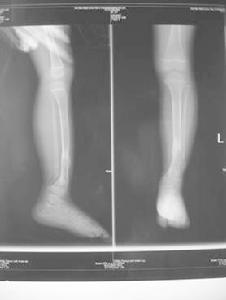

本病主要是進行X線檢查:X線片可見脛骨中、下1/3前彎、成角、纖維囊性變和假關節形成,骨端變細呈錐形,骨端硬化髓腔閉鎖,骨皮質變薄,骨萎縮,脛骨遠端關節面可變形,腓骨可同時有假關節改變或彎曲畸形,小腿短縮。